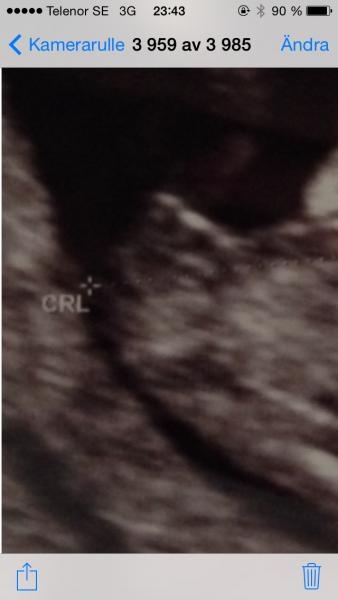

Nubb teori ?!

Enligt nubb teorin så ser det ut som vår lille bebis är en flicka då själva könsnubben ser rak ut. Vad säger ni andra? Har det stämt in på er? Ultraljud från v13

Ja, din är en klockren flicka. Min såg likadan ut i v 14+1 och är enligt läkaren en flicka.

Jasså? Vad kul:) Har en pojke sen innan och tror själv på en till pojke men blev faktiskt lite förvirrad när jag Vsr på ultraljudet ???? Då könet som var "rakt" tittade på min sons ultraljud från v 13 och där var det som redan en liten böjning ????

Ja gissar på pojke, uppdatera gärna!